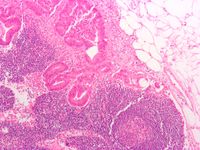

علم الأمراض

Micrograph of a mesenteric lymph node with colorectal adenocarcinoma, the most common type of colorectal cancer.